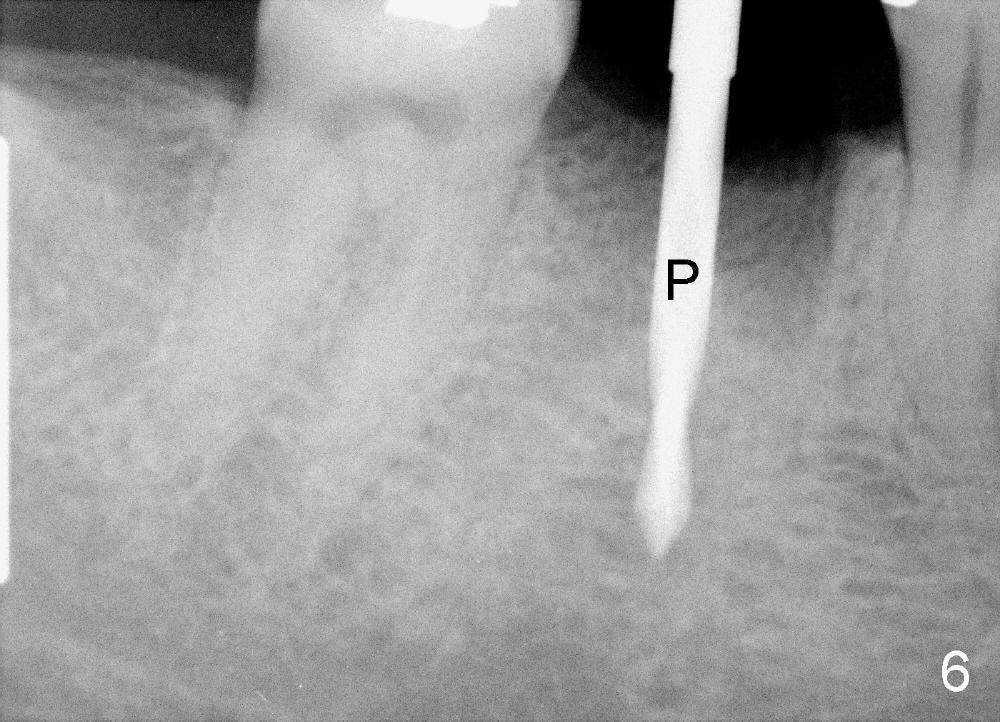

A 38-year-old lady agrees to have implant placement 7 years after loss of the crown of the lower right first molar (Fig.1,2). When the tooth is extracted, the septum is found to be low (Fig.3,4). To confirm it, a PA is taken (Fig.5). To initiate an osteotomy in the septum, it is trans-sectioned with thin osteotomes as shown in Fig.4 insert (black line). A 2 mm pilot drill is placed in the septum (Fig.6: P). The osteotomy is enlarged by 2.5-4.0 mm reamers (Fig.7,8), followed by insertion of 6x17 mm tapered tap at the depth 14 mm (Fig.9). The osteotomy is further enlarged by 4.5 and 5.0 mm reamers. A 6.0x14 mm one piece implant is placed initially. The trajectory is not ideal. A 6.0x14 mm one piece implant is placed initially. The trajectory is not ideal. The implant is removed from the osteotomy partially and reinserted with improved trajectory (Fig.11, compare to Fig.10 (red line)). Primary stability is high. There is not much bone mesiodistally so that the trajectory is easily changed in that direction. After abutment preparation, mixture of autogenous bone (harvested from reamers) and allograft is placed in the residual mesial and distal sockets (Fig.12). To contain the bone graft, an immediate provisional is placed (Fig.13 P). The occlusal plane of the provisional is significantly lower than that of the adjacent teeth to avoid micromovement of the implant. The patient is advised to eat soft food on the left side. Six days postop, the patient returns for prophy. The provisional is removed; the bone graft appears to be incorporating into the socket (Fig.14). After recementation, the provisional remains in place for 3.5 months; PA shows increased bone density in the mesial and distal sockets (Fig.15, compare to Fig.5,11). Due to insurance coverage, the patient defers fabrication of definitive restoration for at least 7 months. The immediate provisional is finally lost 8.5 months postop: the gingiva attaches to the 1-piece implant (Fig.16), while the density of the mesial socket increases (Fig.17 *) with formation of the cortex (lamina dura) coronally (v). Before the provisional (Fig.18 P) is removed for cementation of the definitive restoration, black shadow (*) is noted over the buccal gingiva. It is partially due to buccal placement (Fig.19) and partially due to buccal atrophy over a period of 10.5 months postop. How to prevent buccal placement? Positioning the first pilot drill in the septum buccolingually is a key. Eleven months post crown (Fig.20 C) cementation, the black shadow remains, but there is no tenderness. If the implant threads are immediately underneath the periosteum, there is tenderness.